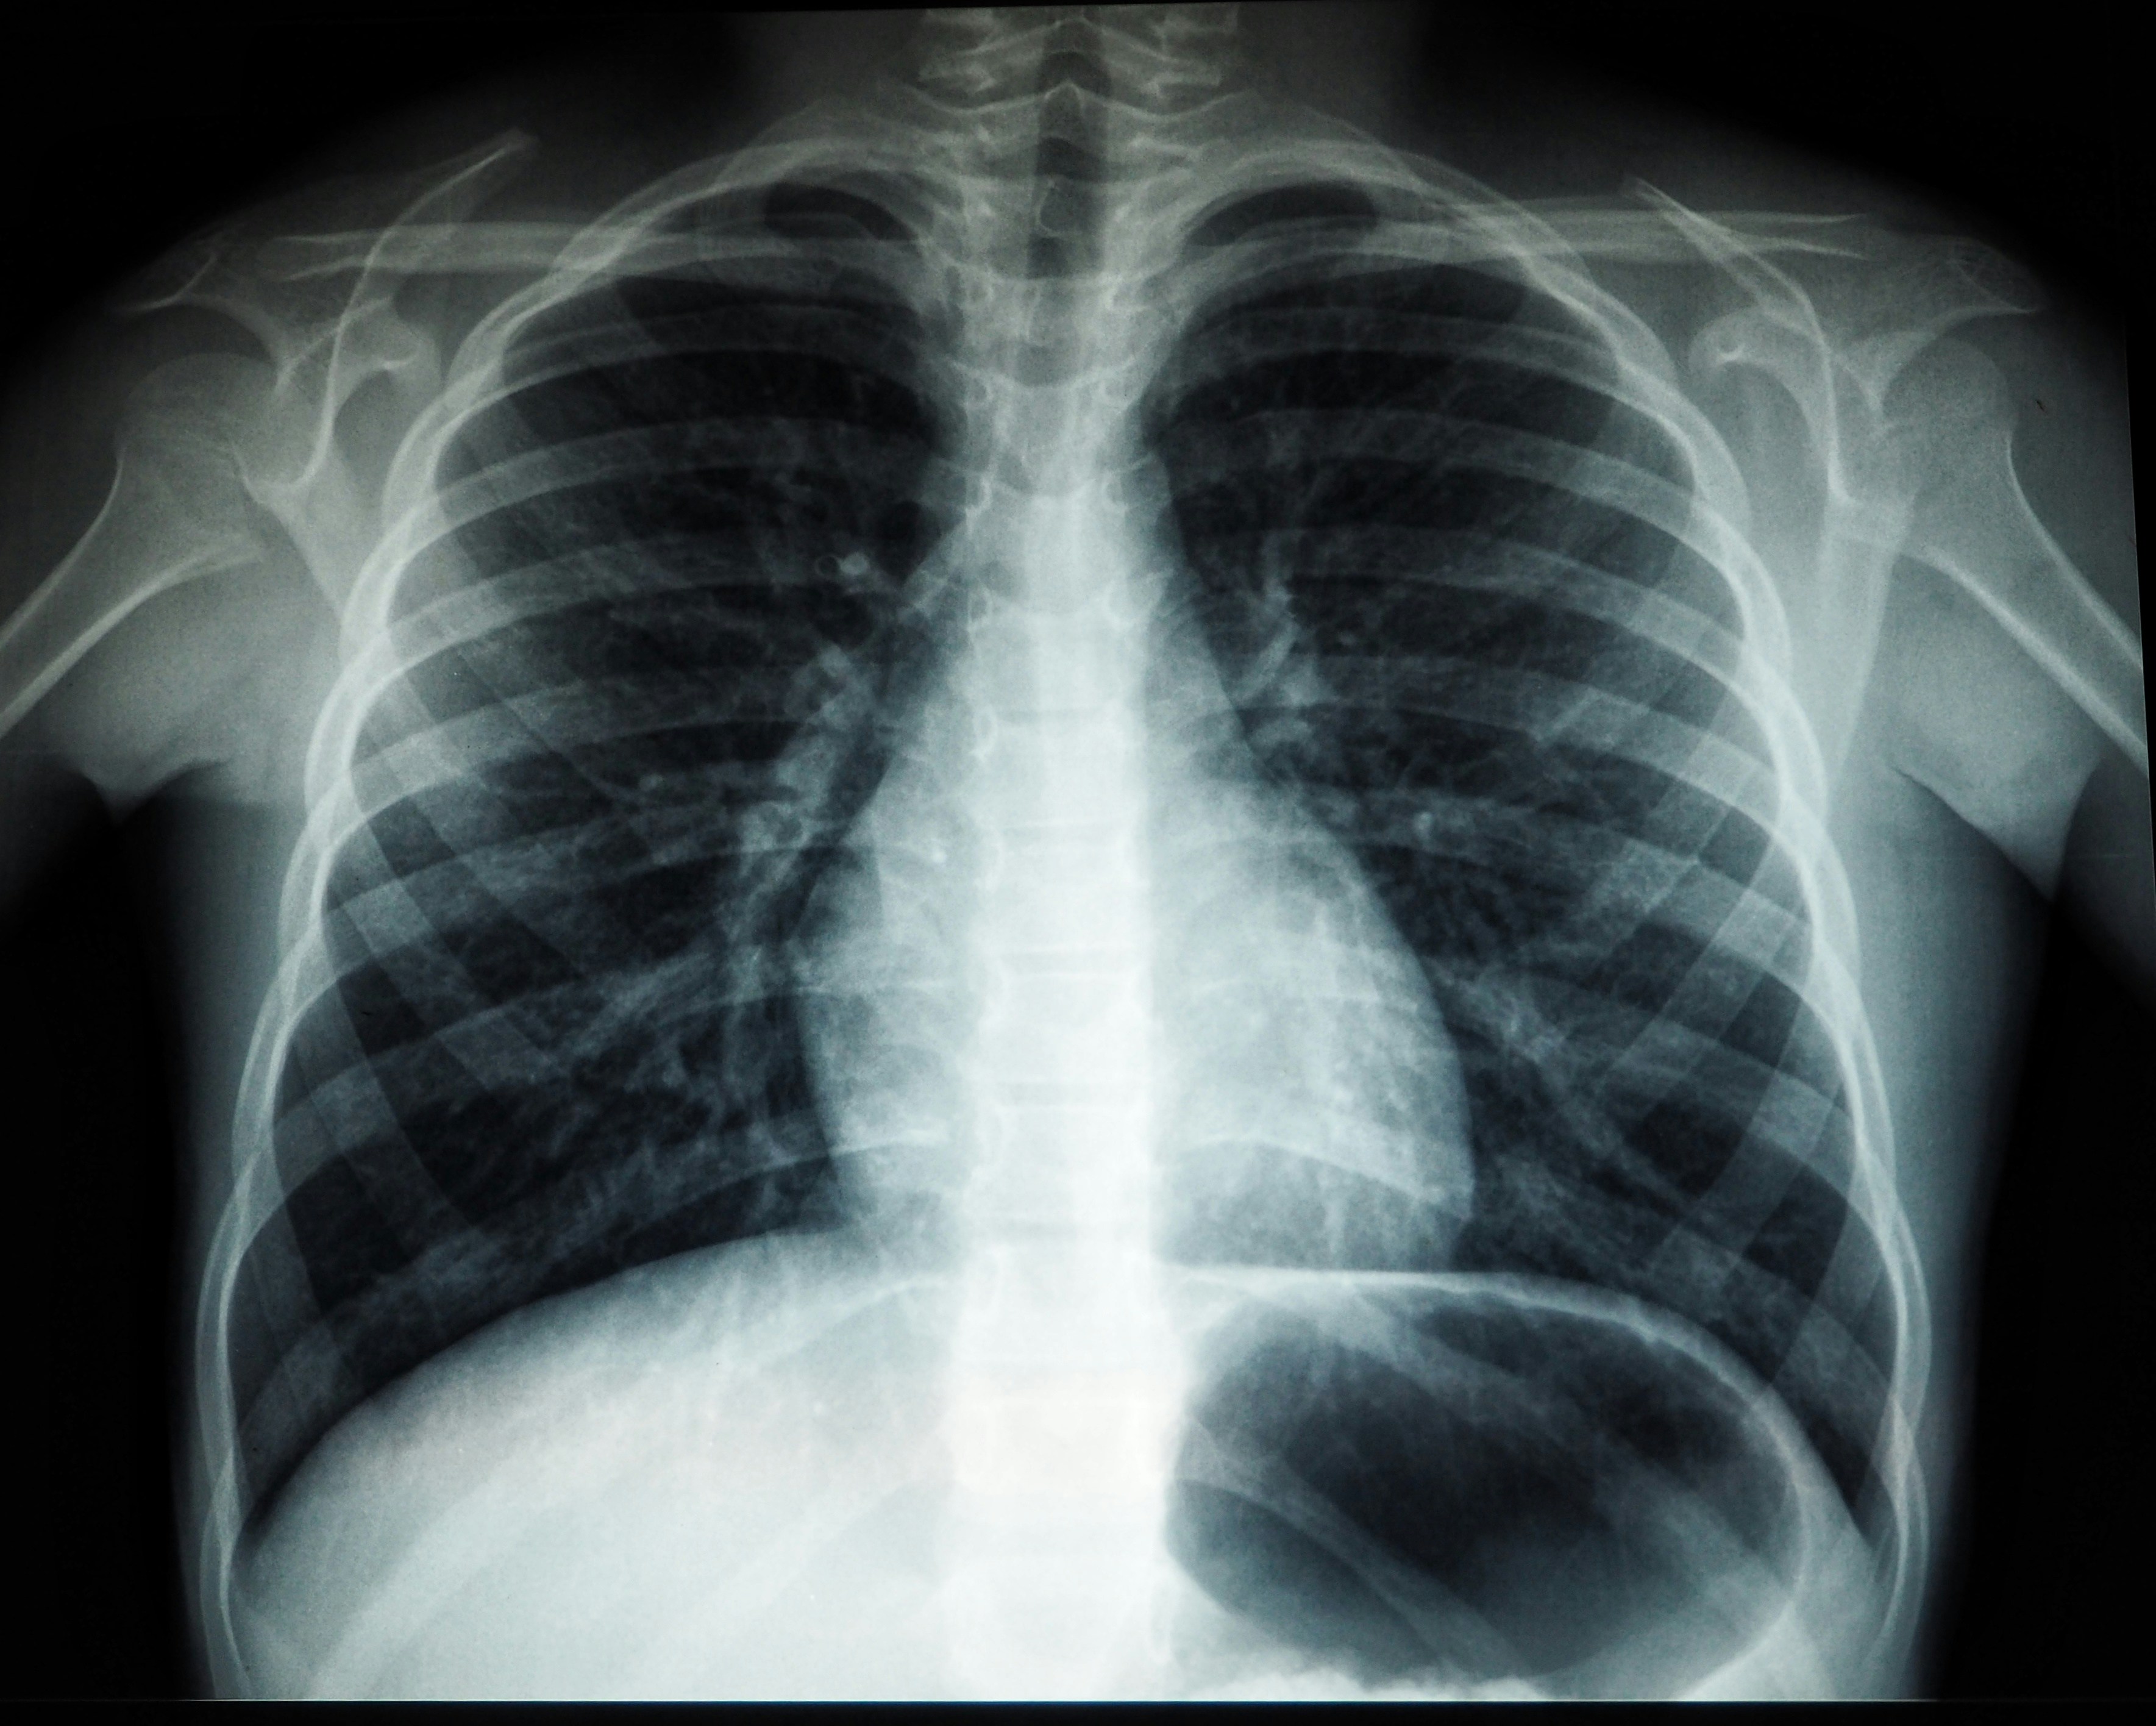

Tanı ve İnflamasyon Oranı

Isı haritasından inflamasyon oranı ve olası tanıları tespit eder.